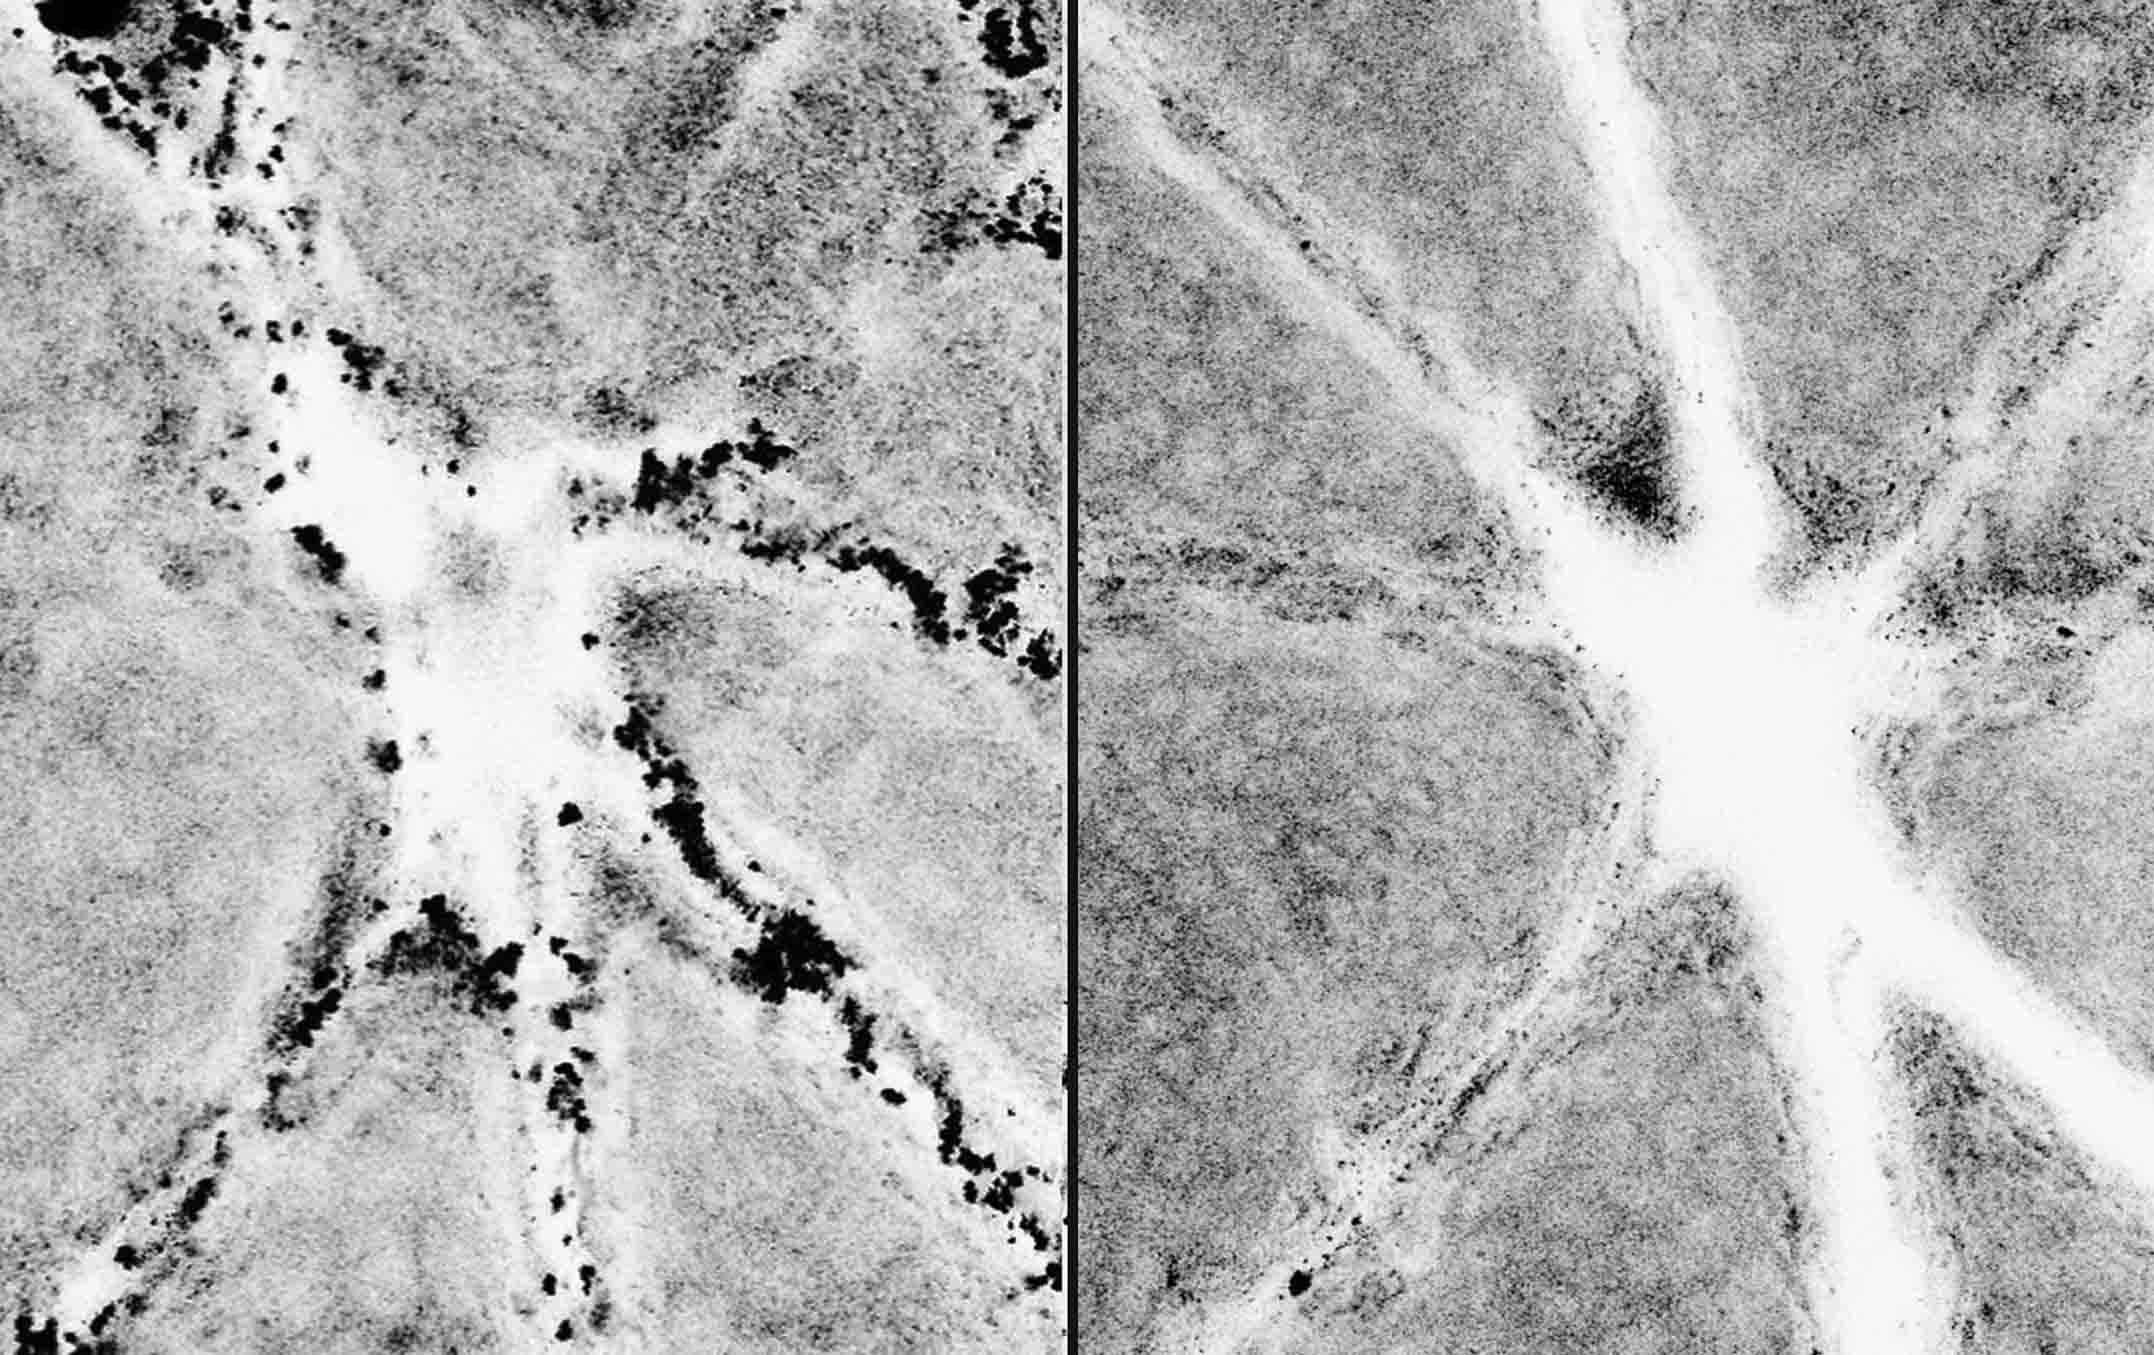

“Three pictures were taken: one before we applied the pollutants, one after application, and the last one after cleansing,” Hugo explains. All in all, an impressive 67,200 images were taken during the trial.

Micro pollutants in the air are so small that they cannot be seen with the naked eye and can penetrate into the skin, which is why a state-of-the-art confocal microscope with 500 times magnification was used, making these "invisible" pollutants visible! If these micro pollutants are allowed to stay and accumulate within the skin, it could lead to many problems such as skin dryness and dullness.

A team of independent experts in the US then analyzed these pictures and compared those cleansed with water and those cleansed with Neutrogena Deep Clean Foaming Cleanser, providing Neutrogena with unbiased, credible results.